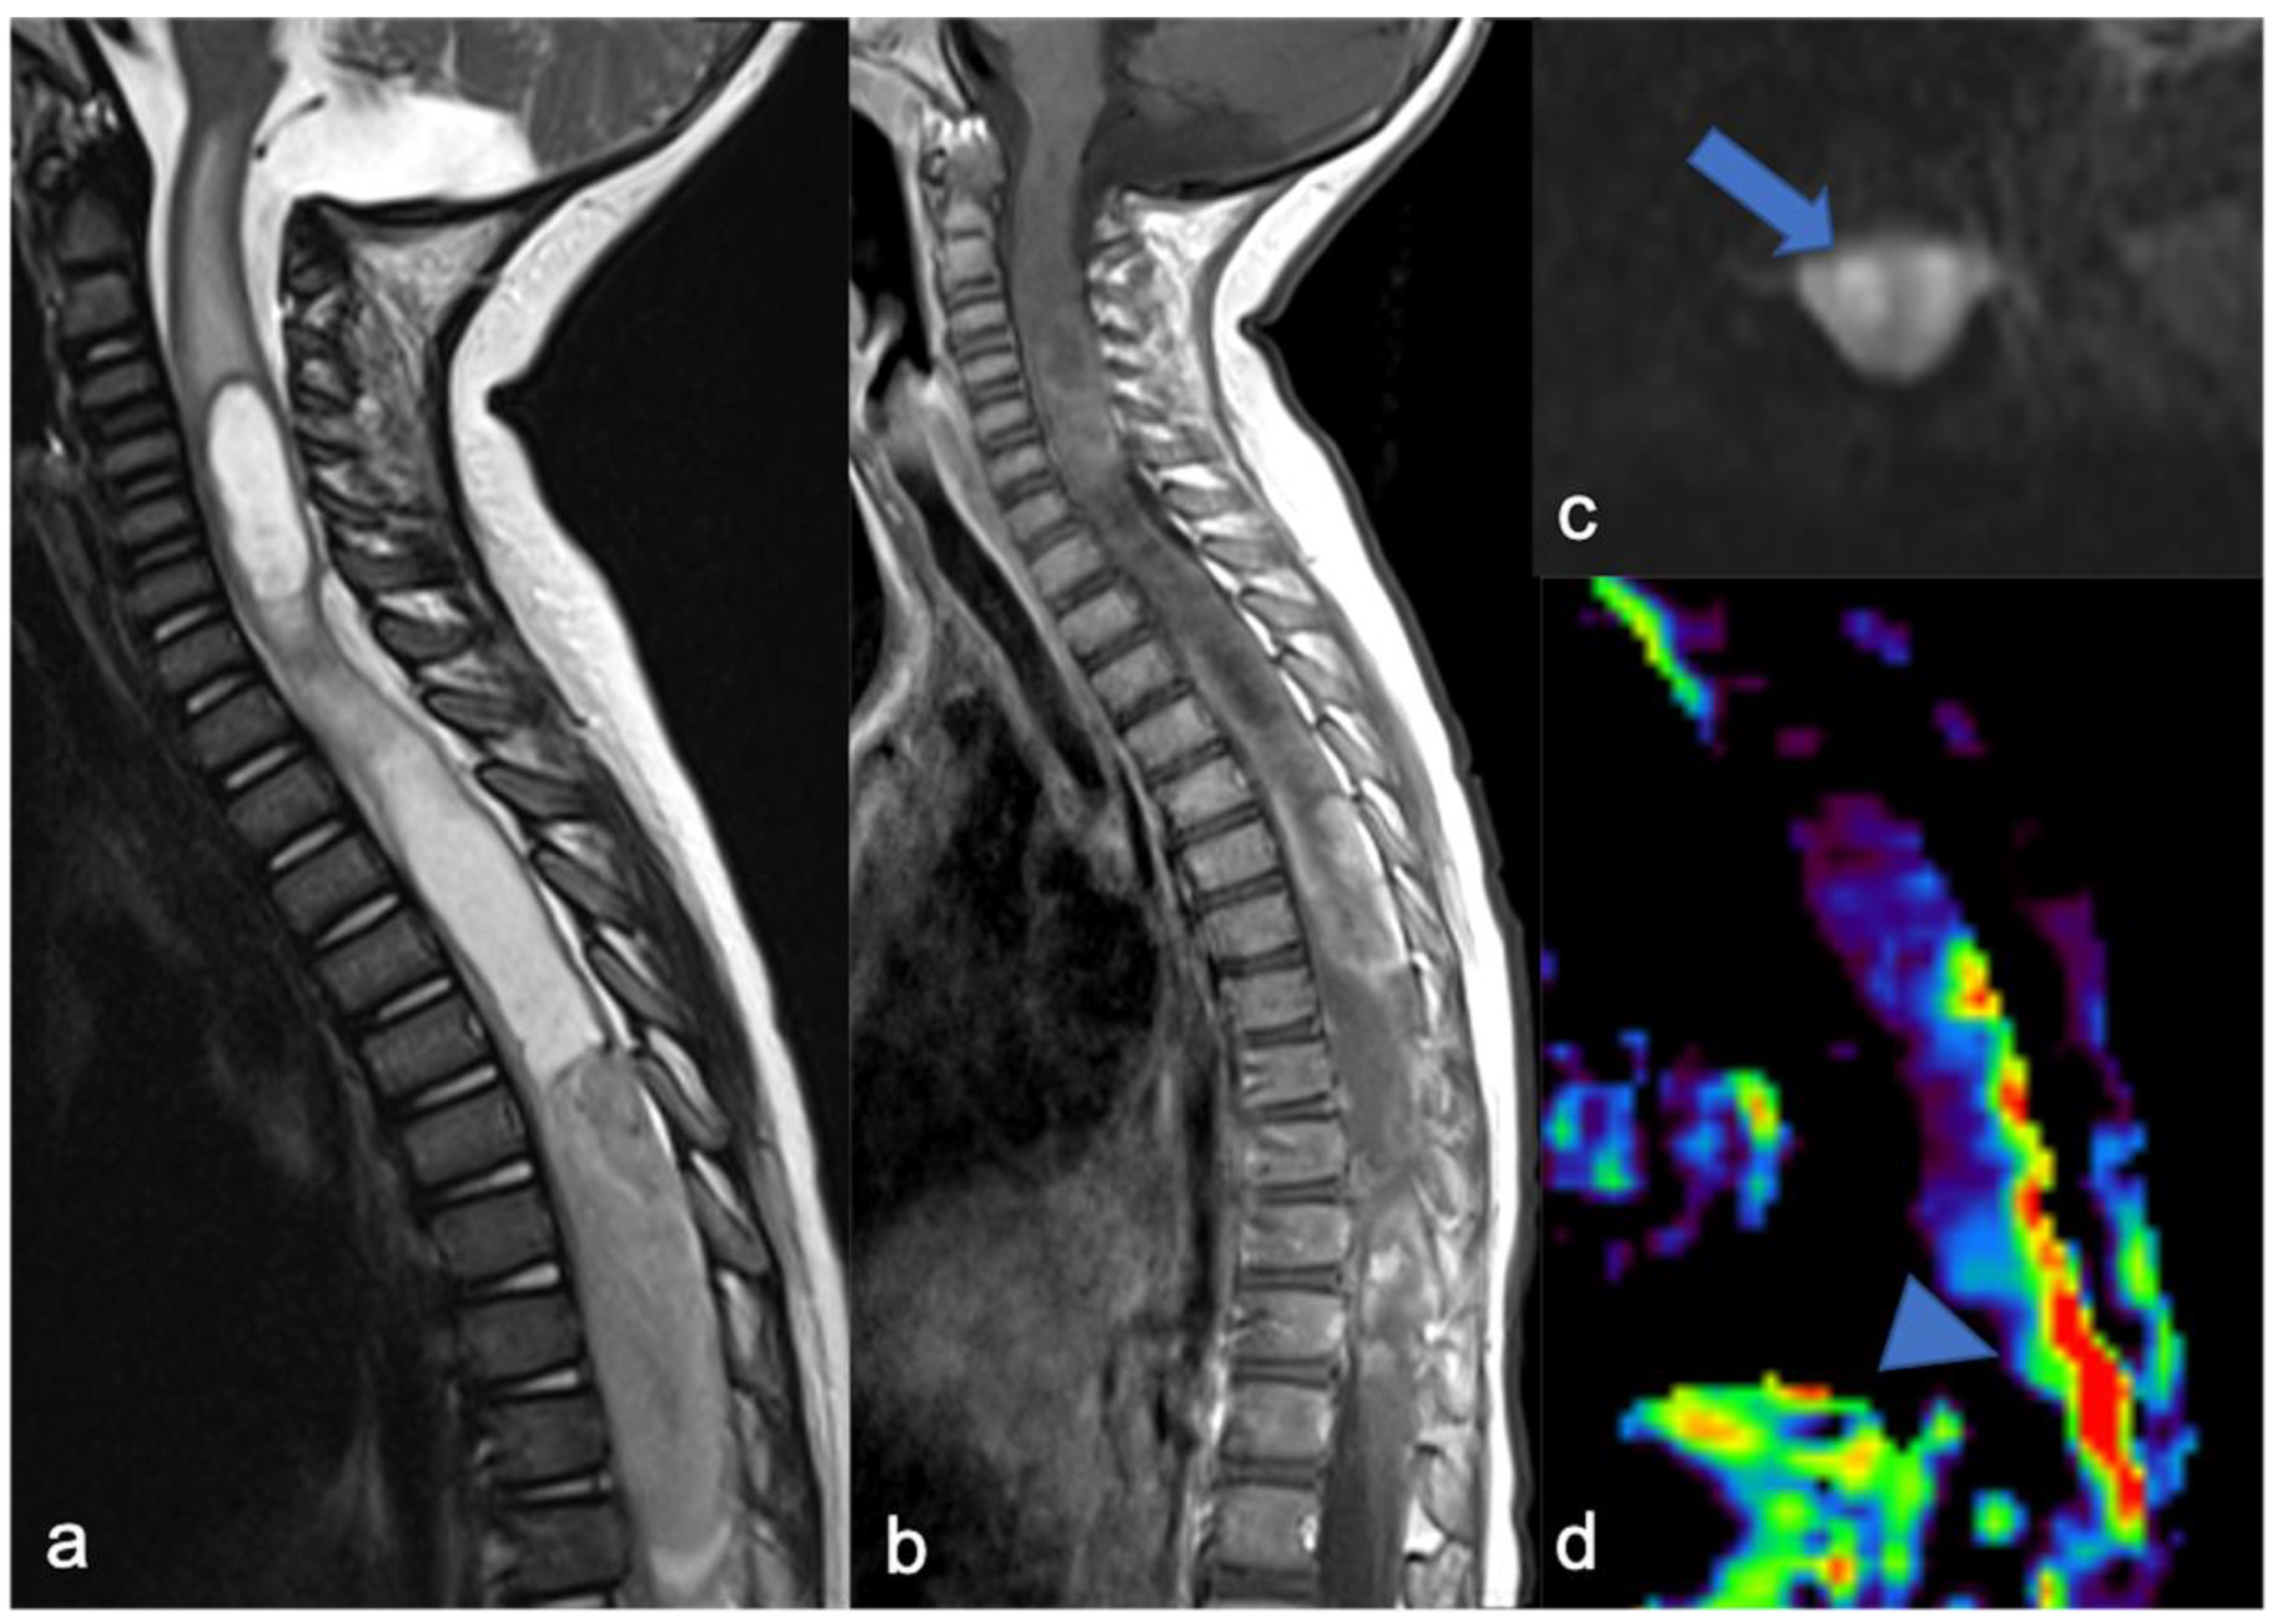

Figure 5.

The same patient as in Figure 4 with high-grade glioma. Intraoperative ultrasound (transversal and longitudinal planes) shows the dorsal solid (a,c) and cystic-like (b,d) components and the cystic/solid transition zone (e).